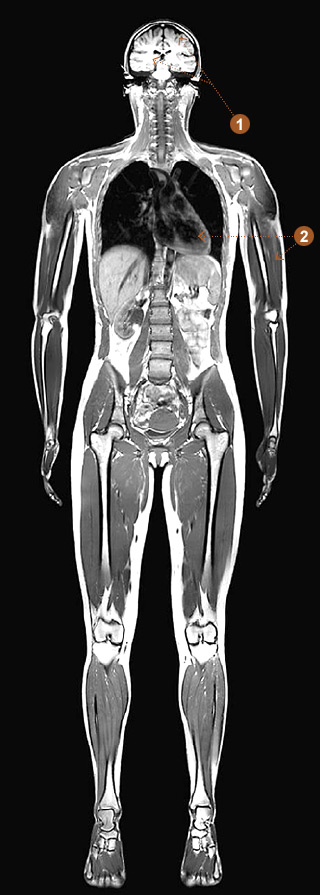

The life-saving medical technology known as Magnetic Resonance Imaging, or MRI, makes detailed images of soft tissue in the body, nearly eliminating the need for exploratory surgery. Unlike X-rays, it can distinguish gray matter from white matter in the brain, cancerous from noncancerous tissue, and muscles from organs, as well as reveal blood flow and signs of stroke.